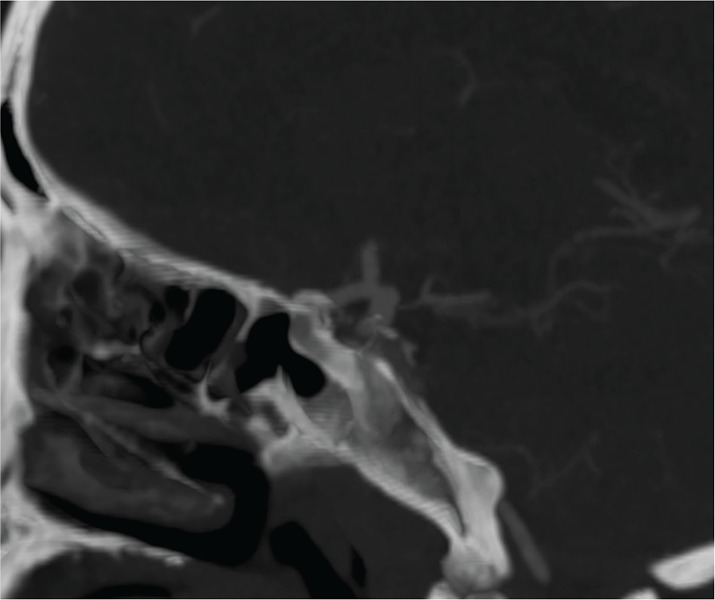

Teaching point: Although computed tomography (CT) is the diagnostic gold standard for acute subdural hematoma, the absence of clear trauma should prompt the use of computed tomography angiography (CTA) to identify potential underlying causes, such as ruptured aneurysms, which can significantly influence treatment decisions.

教学要点:虽然计算机断层扫描(CT)是诊断急性硬膜下血肿的金标准,但如果没有明确的外伤,则应立即使用计算机断层扫描血管造影术(CTA)来识别潜在的潜在病因,如动脉瘤破裂,这对治疗决策有重大影响。